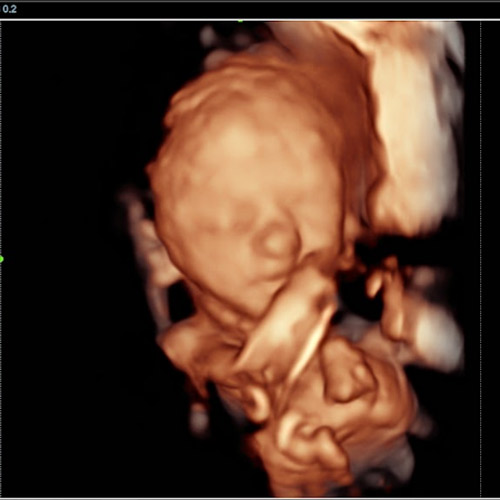

A 3D/4D bonding scan combined with a heartbeat bear near Wakefield offers a unique way to experience both visual and emotional connection before birth.

A 3D scan captures detailed still images of your baby’s face and body, while a 4D baby scan Wakefield allows you to see those images in motion. You may notice movements such as stretching, turning, or subtle expressions, making the experience feel more real.

With a 4D baby ultrasound Wakefield, this technology allows you to see your baby with greater clarity and depth. The result is softer, more lifelike visuals that can feel closer to a photograph than a traditional scan.

- Improved Detail - Clearer definition of facial features

- Natural Appearance - Enhanced depth and shading

Our Scans